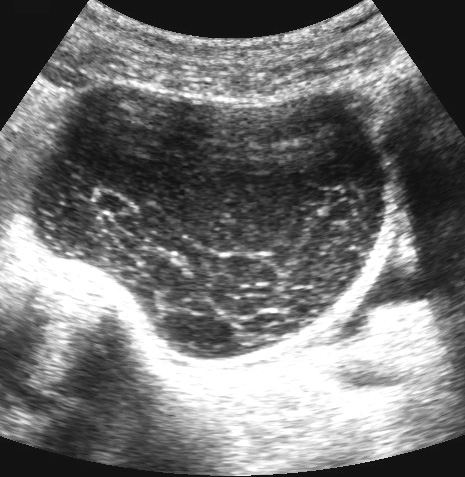

Ca lâm sàng 5

Các nang xuất huyết tồn lưu thường chứa các khối đặc, không có mạch máu, không đồng nhất, đại diện cho cục máu đông.

Sự co rút của các cục máu đông này thường tạo ra các bờ lõm (đầu mũi tên).